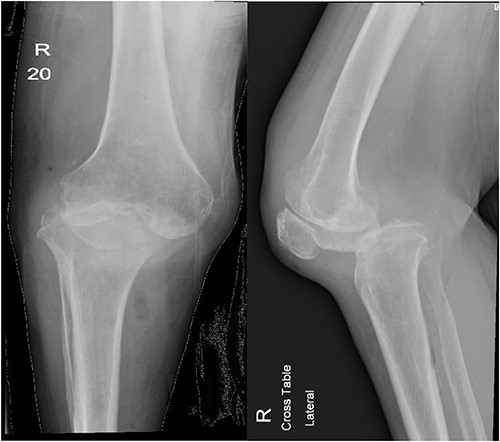

After 1-week from discharge, she presented to ED with 2 days history of right leg swelling and tenderness despite being bedbound for 3 months and denying any history of trauma. Her physical exam showed right knee swelling with absent posterior tibial artery pulse. Because of her mobility status, there was a suspicion of deep vein thrombosis (DVT); therefore, doppler ultrasound was obtained along with knee X-ray and computed tomography (CT) runoff (Fig. 1). Her doppler ultrasound showed negative results; however, knee X-ray showed posterolateral knee dislocation and CT runoff revealed evidence of septic arthritis of right knee with large intramuscular abscess extending from the popliteal fossa down to above the ankle joint adjacent to the Achilles tendon. The patient then was shifted to OR for a third I&D and a spanning external fixator application to allow for soft tissue to form enough fibrosis in order to keep the joint stable and avoid further major surgeries. At her 6-week follow-up, the external fixator was removed and the patient’s assessment showed stable knee joint and unremarkable, pre- and post-external fixator removal and X-ray.

Anteroposterior and lateral views of the knee at second presentation.